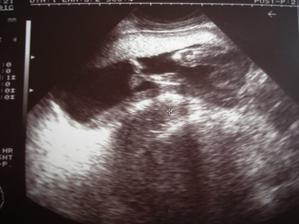

13.9. jsem dělala první testík a málem jsem přehlédla tu slabounkou čárku. Byl to menší šok, jelikož se o miminko už rok snažíme. Následující den jsem udělala další testík pro potvrzení a z nevolnosti už mi bylo více než jasné, že bude čárka silnější-a také že ano. První utz. 25.9. - 5+2tt mimi má 17mm. Druhý utz. 18.10. - 9+1tt mimi má 23,3mm. Třetí utz. 6.11. - 11+2tt. Čtvrtý utz. 29.11 - 14+4tt Malé má 16 cm. 16tt-16+3tt jsem přibrala 2 kila a začínám se pěkně cpát.Na utz. s námi byla nastávající babička. 20tt jsem zatím přibrala 4.5 kg. 21 tt další utz., váha 59kg. To s námi byl na utz. i tatínek. Začínající váha byla 53kg. 25tt kontrolní utz. 61kg. Miminko je zatím stále zadečkem dole.Tak máme 36tt, miminko už je otočené hlavičkou dole a já mám 65,5 kg. Přecházíme k doktorovi do nemocnice a čekáme kdy se prcek rozhodne přijít mezi nás, podle pana doktora to má být ještě před termínem 🙂